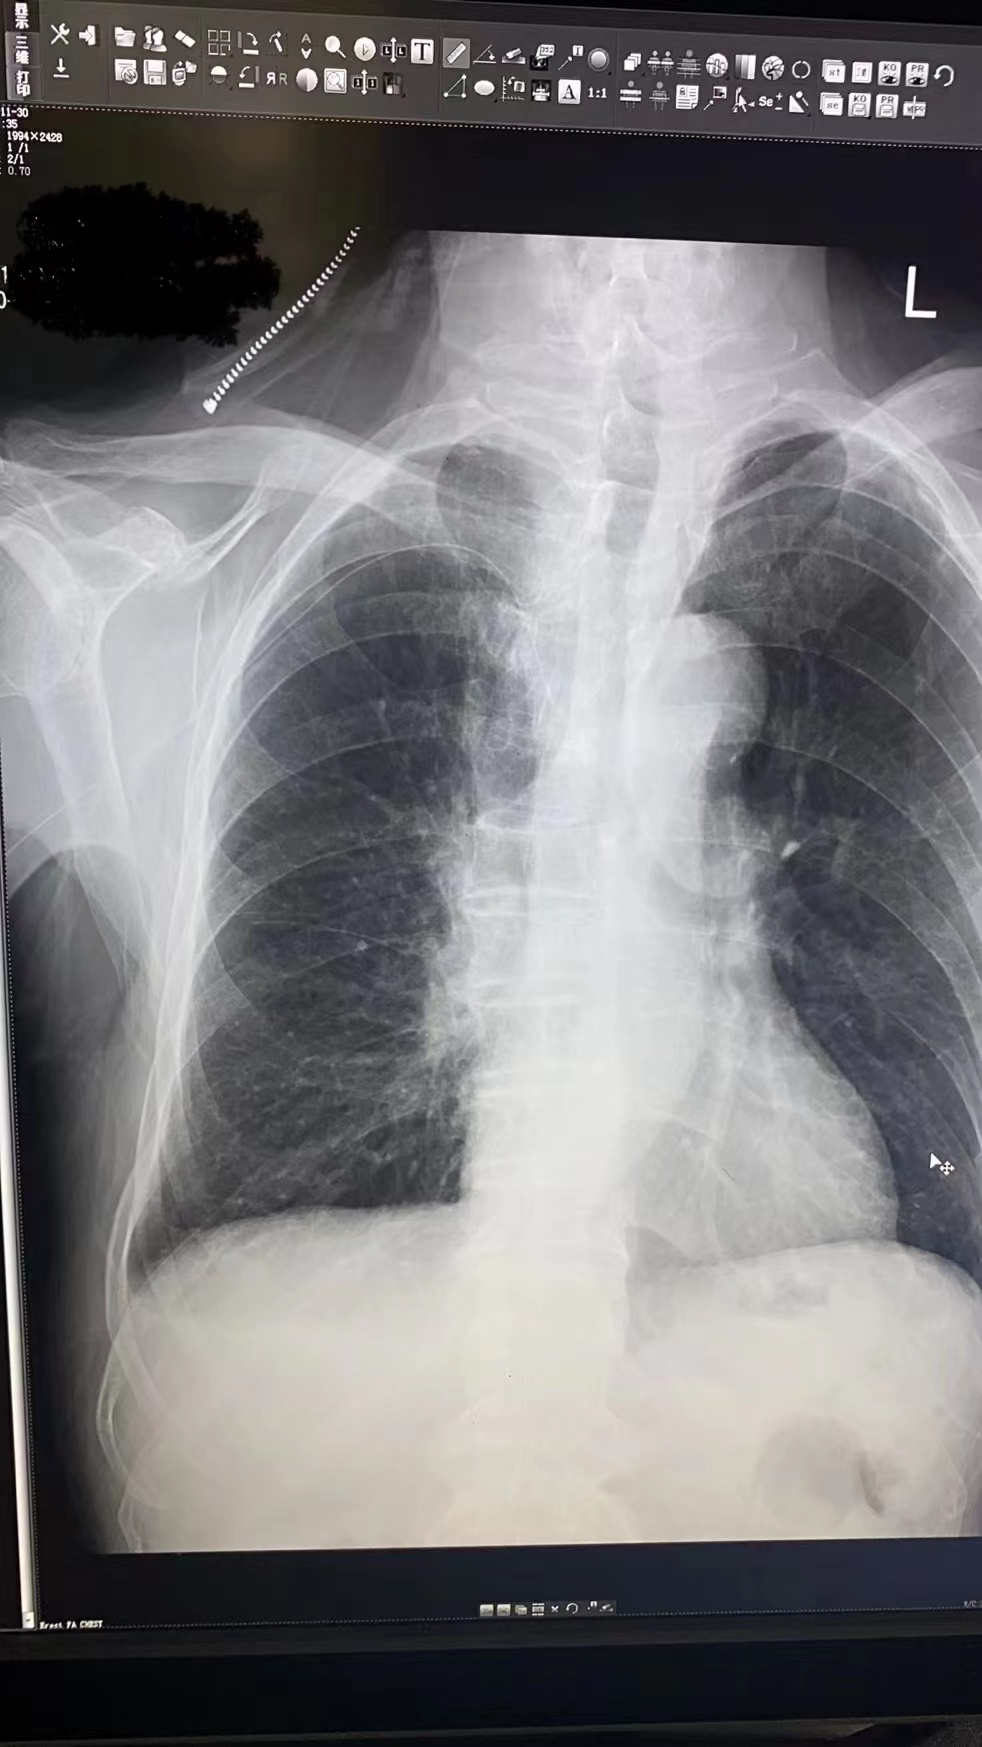

事情要从高大伯因“左肺恶性肿瘤”住院说起,医生分析了病情为其制定治疗方案——化疗。在治疗开始前需要进行经外周静脉穿刺中心静脉置管术(PICC),静疗专项小组组长冯尼尼和外科徐锦艳护士长在充分评估患者病情及血管条件后为高大伯进行PICC穿刺,穿刺过程很顺利,但在导管置入25cm时,遇到阻力,置入后回弹,出现置管困难,在反复多次调节体位,边冲管边置管等多种尝试下,成功置入。半小时拍片定位显示,患者PICC导管位于右侧腋窝区,导管在右锁骨下静脉返折。考虑原因:血管畸形、官腔狭窄、肿瘤站位压迫血管等,再次调整重新置管,出现导管反折致导管异位的概率很高。

正当我们为此一筹莫展之际,放射科冯国灿主任建议我们可以利用数字减影血管造影技术(DSA)进行调整置管,这个建议让我们看到了希望。我们本着以“患者为中心,患者利益至上”的原则,通过对DSA技术的原理和仪器的操作进行全面学习,并在放射科的配合下和心内科郭张财主任的指导下,成功置管,保障患者治疗方案正常开展。